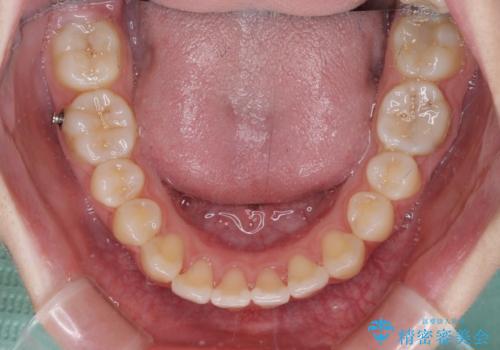

- 前歯の叢生と上顎左右の八重歯を気にして来院された患者様です。

奥歯の咬み合わせを見ると、左側は上顎が下顎に対して相対的に前方にあり、上下の前歯が接触していない状態でした。

咬み合わせを改善するためには、左側上顎臼歯を後方に移動させた咬み合わせにする必要があります。

インビザライン単体で改善することも可能性もありますが、インビザライン単体で達成する可能性が低いと考えられたため、カリエール・ディスタライザーという補助装置を併用して、より確実性を上げることとしました。

奥歯の咬み合わせを改善しながら、並行してインビザラインで歯列を整えることとしました。

カリエールディスタライザーを併用したことで、左側臼歯の咬み合わせを確実に改善させることができました。